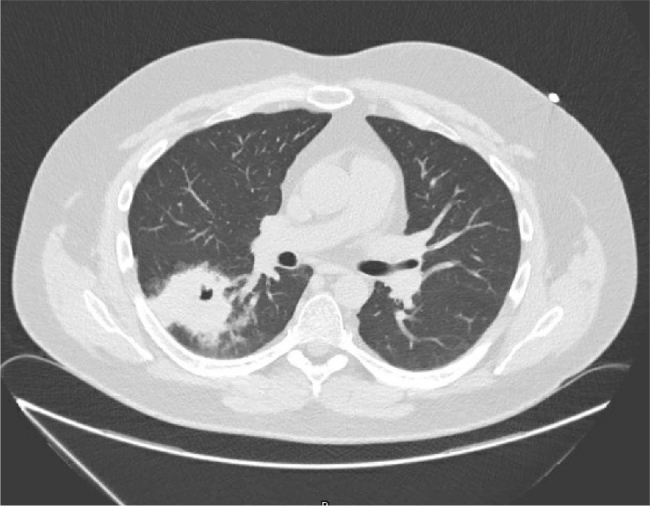

Case description: We report the case of a 29-year-old male who presented with new-onset diabetes mellitus, resistant hypertension and significant weight gain. Physical examination revealed features consistent with Cushing's syndrome. Biochemical evaluation confirmed ACTH-dependent hypercortisolism with an elevated plasma ACTH level, and a lack of suppression on high-dose dexamethasone testing; imaging identified a suspicious pulmonary nodule. Bronchoscopic biopsy revealed no malignancy, however cultures grew Rhodococcus species. The patient denied any respiratory symptoms or environmental exposure. Initial antibiotic therapy with ciprofloxacin and rifampin was started. Follow-up imaging showed rapid enlargement of the pulmonary mass, prompting surgical resection. Histopathology revealed malakoplakia, and repeat cultures again yielded Rhodococcus spp. Antibiotics were adjusted to azithromycin and rifampin, and the patient was started on ketoconazole to manage hypercortisolism.